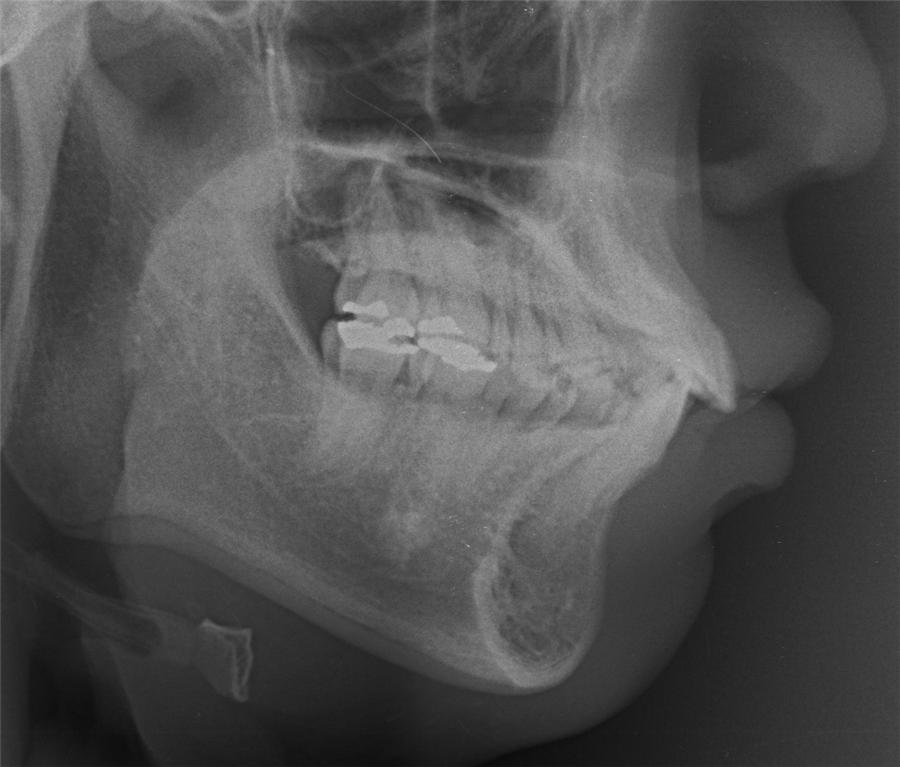

네... 사진 잘 보았습니다. 고민이 많이 되겠군요. 님의 상태는 일반적인 돌출입 부정교합이라고 판단이 됩니다. 그리 어려운 요소도 없구요. 일반적인 브라켓 교정치료로 진행하여도 1년반에서 2년 사이정도에서 교정이 이뤄지리라 예상이 됩니다. 님이 문의하신 교정법들은 치아의 이동을 좀더 빠르게 하는 조치들 인데요. 대략 6개월정도의 단축 효과정도 있으리라 생각이 됩니다. 즉, 1년 남짓정도는 걸리게 되지요. 1번과 3번의 치료방법은 수술의 심적인 부담이 많은 편이랍니다. 2번의 치료는 돌출된 입의 선행적인 치료가 장점이고 치료기간의 메리트는 그리 없지요. 저의 경우는 킬본 교정이라는 장치를 사용하여 2번의 방식데로 치료를 하는 경우가 많이 있는데 주 목적은 치료기간의 단축에 있는 것이 아니라 잇몸돌출의 해소와 앞서 언급한 돌출의 선행적인 해소에 있답니다. 4번의 방법은 님이 진동기를 일정시간 물고 있는 것인데 저는 사용을 하지 않아 뭐라 말씀을 드리기가 그렇습니다. 어쨋든 1번부터 4번까지의 치료는 특별한 부작용이 있는 치료들은 아니랍니다. 님이 언급한 교정치료 중의 애로사항인 심미적인 부분은 장치의 위치를 안으로하는 방법등을 고려해 볼 수 있구요. 발음은 교정치료 후 3개월 정도 되면 대부분 적응을 하는 것 같습니다. 참고가 되셨는지 모르겠네요...^^